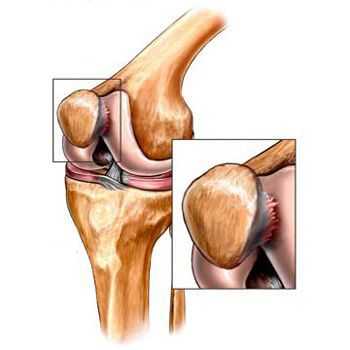

Разрыв внутреннего мениска по типу «ручки лейки» с блоком коленного сустава (невозможность полностью разогнуть коленный сустав). На фотографии хорошо виден крупный фрагмент мениска плотно зажатый между суставными поверхностями бедренной и большеберцовой кости.

Одним из наиболее характерных ви- дов вертикальных разрывов являются продольные разрывы со смещением оторванной части — разрывы по типу «ручки лейки» или «ручки ковша». Эти разрывы характеризуются отделением центрального фрагмента мениска и смещением его медиально в межмыщелковую ямку или кпереди над передним рогом мениска. Отделенный центральный фрагмент имеет визуальное сходство с ручкой лейки или ковша. Эти разрывы составляют около 10 % всех разрывов менисков и чаще наблюдаются в медиальном мениске.